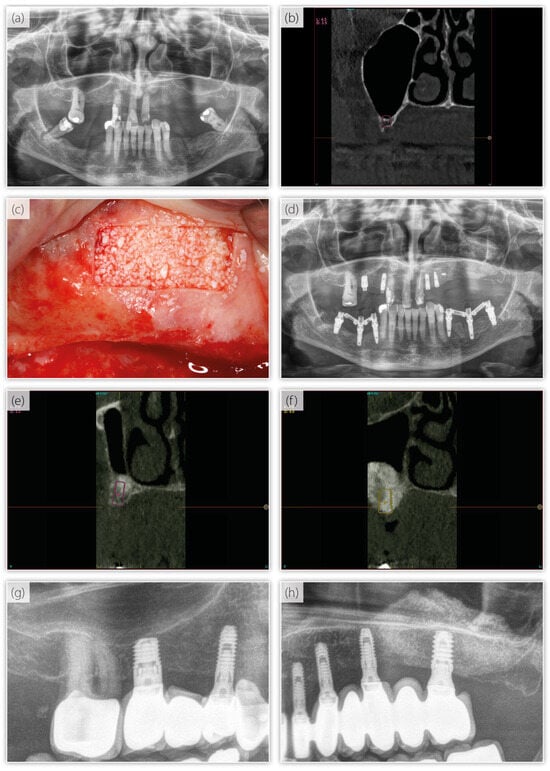

| Variable | Lateral Sinus Elevation Group | Short Implants Group | p-Value | |

|---|---|---|---|---|

| Number of implants | 39 | 32 | ||

| Bone density (median; range) | 700 (300–1100) | 450 (100–700) | 0.071 a | |

| Mesial MBL b (mm) (median; range) | loading | 0.0 (−1.6 to 0.3) | 0.0 (−0.71 to 0.0) | 0.088 a |

| Distal MBL b (mm) (median; range) | −0.4 (−2.2 to 0.0) | −0.4 (−0.8 to 0.0) | 0.789 a | |

| Mesial MBL b (mm) (median; range) | Last radiograph | 0.7 (−3.9 to 0.0) | 0.4 (−1.0 to 0.0) | 0.005 a |

| Distal MBL b (mm) (median; range) | −0.8 (−3.2 to 0.4) | −0.7 (−3.1 to 0.0) | 0.155 a | |

| Variation in MBL b–mesial (mm) (median; range) | −0.3 (−3.9 to 0.1) | −0.2 (−1.0 to 0.1) | 0.092 a | |

| Variation in MBL b–distal (mm) (median; range) | −0.4 (−3.2 to 0.8) | −0.2 (−2.8 to 0.32) | 0.196 a | |

| Implant failure (frequency) | 0 | 1 | 0.45 c | |

| Mucositis | 2 | 0 | 0.498 c |